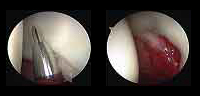

Arthroscopy provides a good way to address problems within the hip joint with less tissue damage and faster recovery and comfort.

- What is hip arthroscopy?

Arthroscopy is a surgical procedure to explore, diagnose and treat problems inside a joint. It involves inserting an optical system with a light source connected to a digital camera to visualize intra-articular structures. - What are the most common injuries treated with hip arthroscopy?

- Loose bodies, articular cartilage and small fragments that break off and damage the joint

- Labral injuries or acetabular labrum

- Injuries of the articular cartilage surrounding the femoral head, causing irregularities in the surface contact between the femur and acetabulum

- How is arthroscopic surgery performed?

Hip arthroscopy is performed under general anesthesia. The patient usually stays overnight, although the trend is gradually changing to outpatient surgery.